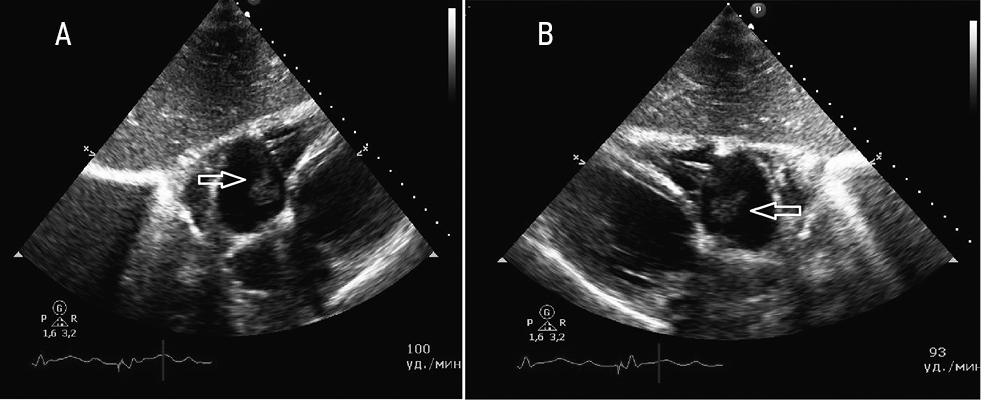

By April 2019, the patient’s condition deteriorated rapidly: weight loss (-8 kg), febrile rises in temperature, enlargement of the liver and spleen, severe weakness, a tendency to arterial hypotension (90–80/60–55 mm Hg), severe anemia, lungs X-ray showed pneumonic infiltration again. Blood tests revealed an increase in anemia, thrombocytosis, leukocytosis, and an increase in ESR by 4.2 times. The growth of Staphylococcus epidermidis was noted in blood cultures. ECG revealed large loose vegetation on the electrodes in the immediate vicinity of the MC (Fig. 3), however, there were no reliable signs of the involvement of MCs in the infectious process.

Fig. 3. Echocardiogram of patient A., 04.2019 A — Four-chambered apical section; B — Three-chambered subcostal modified section. The arrows indicate a large loose vegetation located on the electrode near the TV structures.